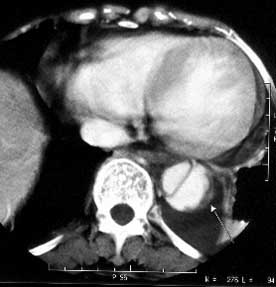

女性,71岁,胸骨后疼痛两小时来诊。体检:心界左下扩大,心率70次/每分,律齐,无杂音。x线胸片示:纵隔增宽。

ct平扫:降主动脉全程约18cm范围内管腔扩张,管腔被条索影分隔成前内、外后两腔,条索影与管壁连接处见散在点状钙化影。

增强扫描:见前内腔较小,与主动脉弓同步强化;后外腔较大,造影剂消退时间教主动脉弓延长,切管壁不均匀增厚,强化不明显。

ct诊断:降主动脉夹层动脉瘤,伴附壁血栓形成。